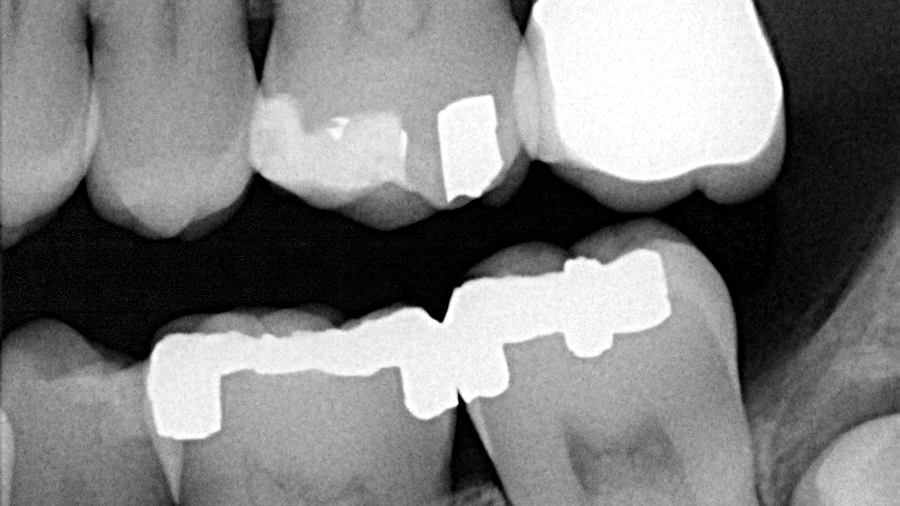

A healthy, 38-year-old male presented to the office for a comprehensive exam. His blood pressure was within normal limits, and no medications were being taken. Bitewing radiographs were taken, and it was noted that there was a cystlike lesion on what appeared to be a mesial impaction of no. 17. A panoramic radiograph indeed revealed a large, radiolucent/cystlike lesion surrounding a mesial/inferior-positioned no. 17. The widest point of the cyst measured approximately 3 cm. The patient reported knowing about the lesion but was not inclined to have it removed because it was not bothering him. The area was not tender to palpation; tooth no. 18 had normal pocketing and tested normal to cold, percussion, and bite.

Dentigerous cyst. A dentigerous cyst is “an odontogenic cyst that surrounds the crown of an impacted tooth, caused by fluid accumulation between the reduced enamel epithelium and enamel surface, resulting in a cyst in which the crown is located within the lumen and root(s) outside.”1 Typically, dentigerous cysts remain asymptomatic, but large growths have been known to produce swelling and pain. The most common teeth involved are the unerupted maxillary and mandibular third molars or maxillary cuspids.1 The highest incidence occurs during the second and third decades of life.2 The recommended treatment is complete enucleation, which reduces the possibility of potentially dangerous cells remaining in the region after surgery to form residual cysts, ameloblastomas, or other lesions.2

In this particular case, the patient was referred to an oral surgeon and the lesion was removed. Histology confirmed the diagnosis, and the patient has been seen on a regular basis without any complications or recurrent lesions. The bone has filled in nicely and no. 18 is vital. The coronal portion of no. 32 was removed due to the wrapping of the roots around the inferior alveolar nerve.